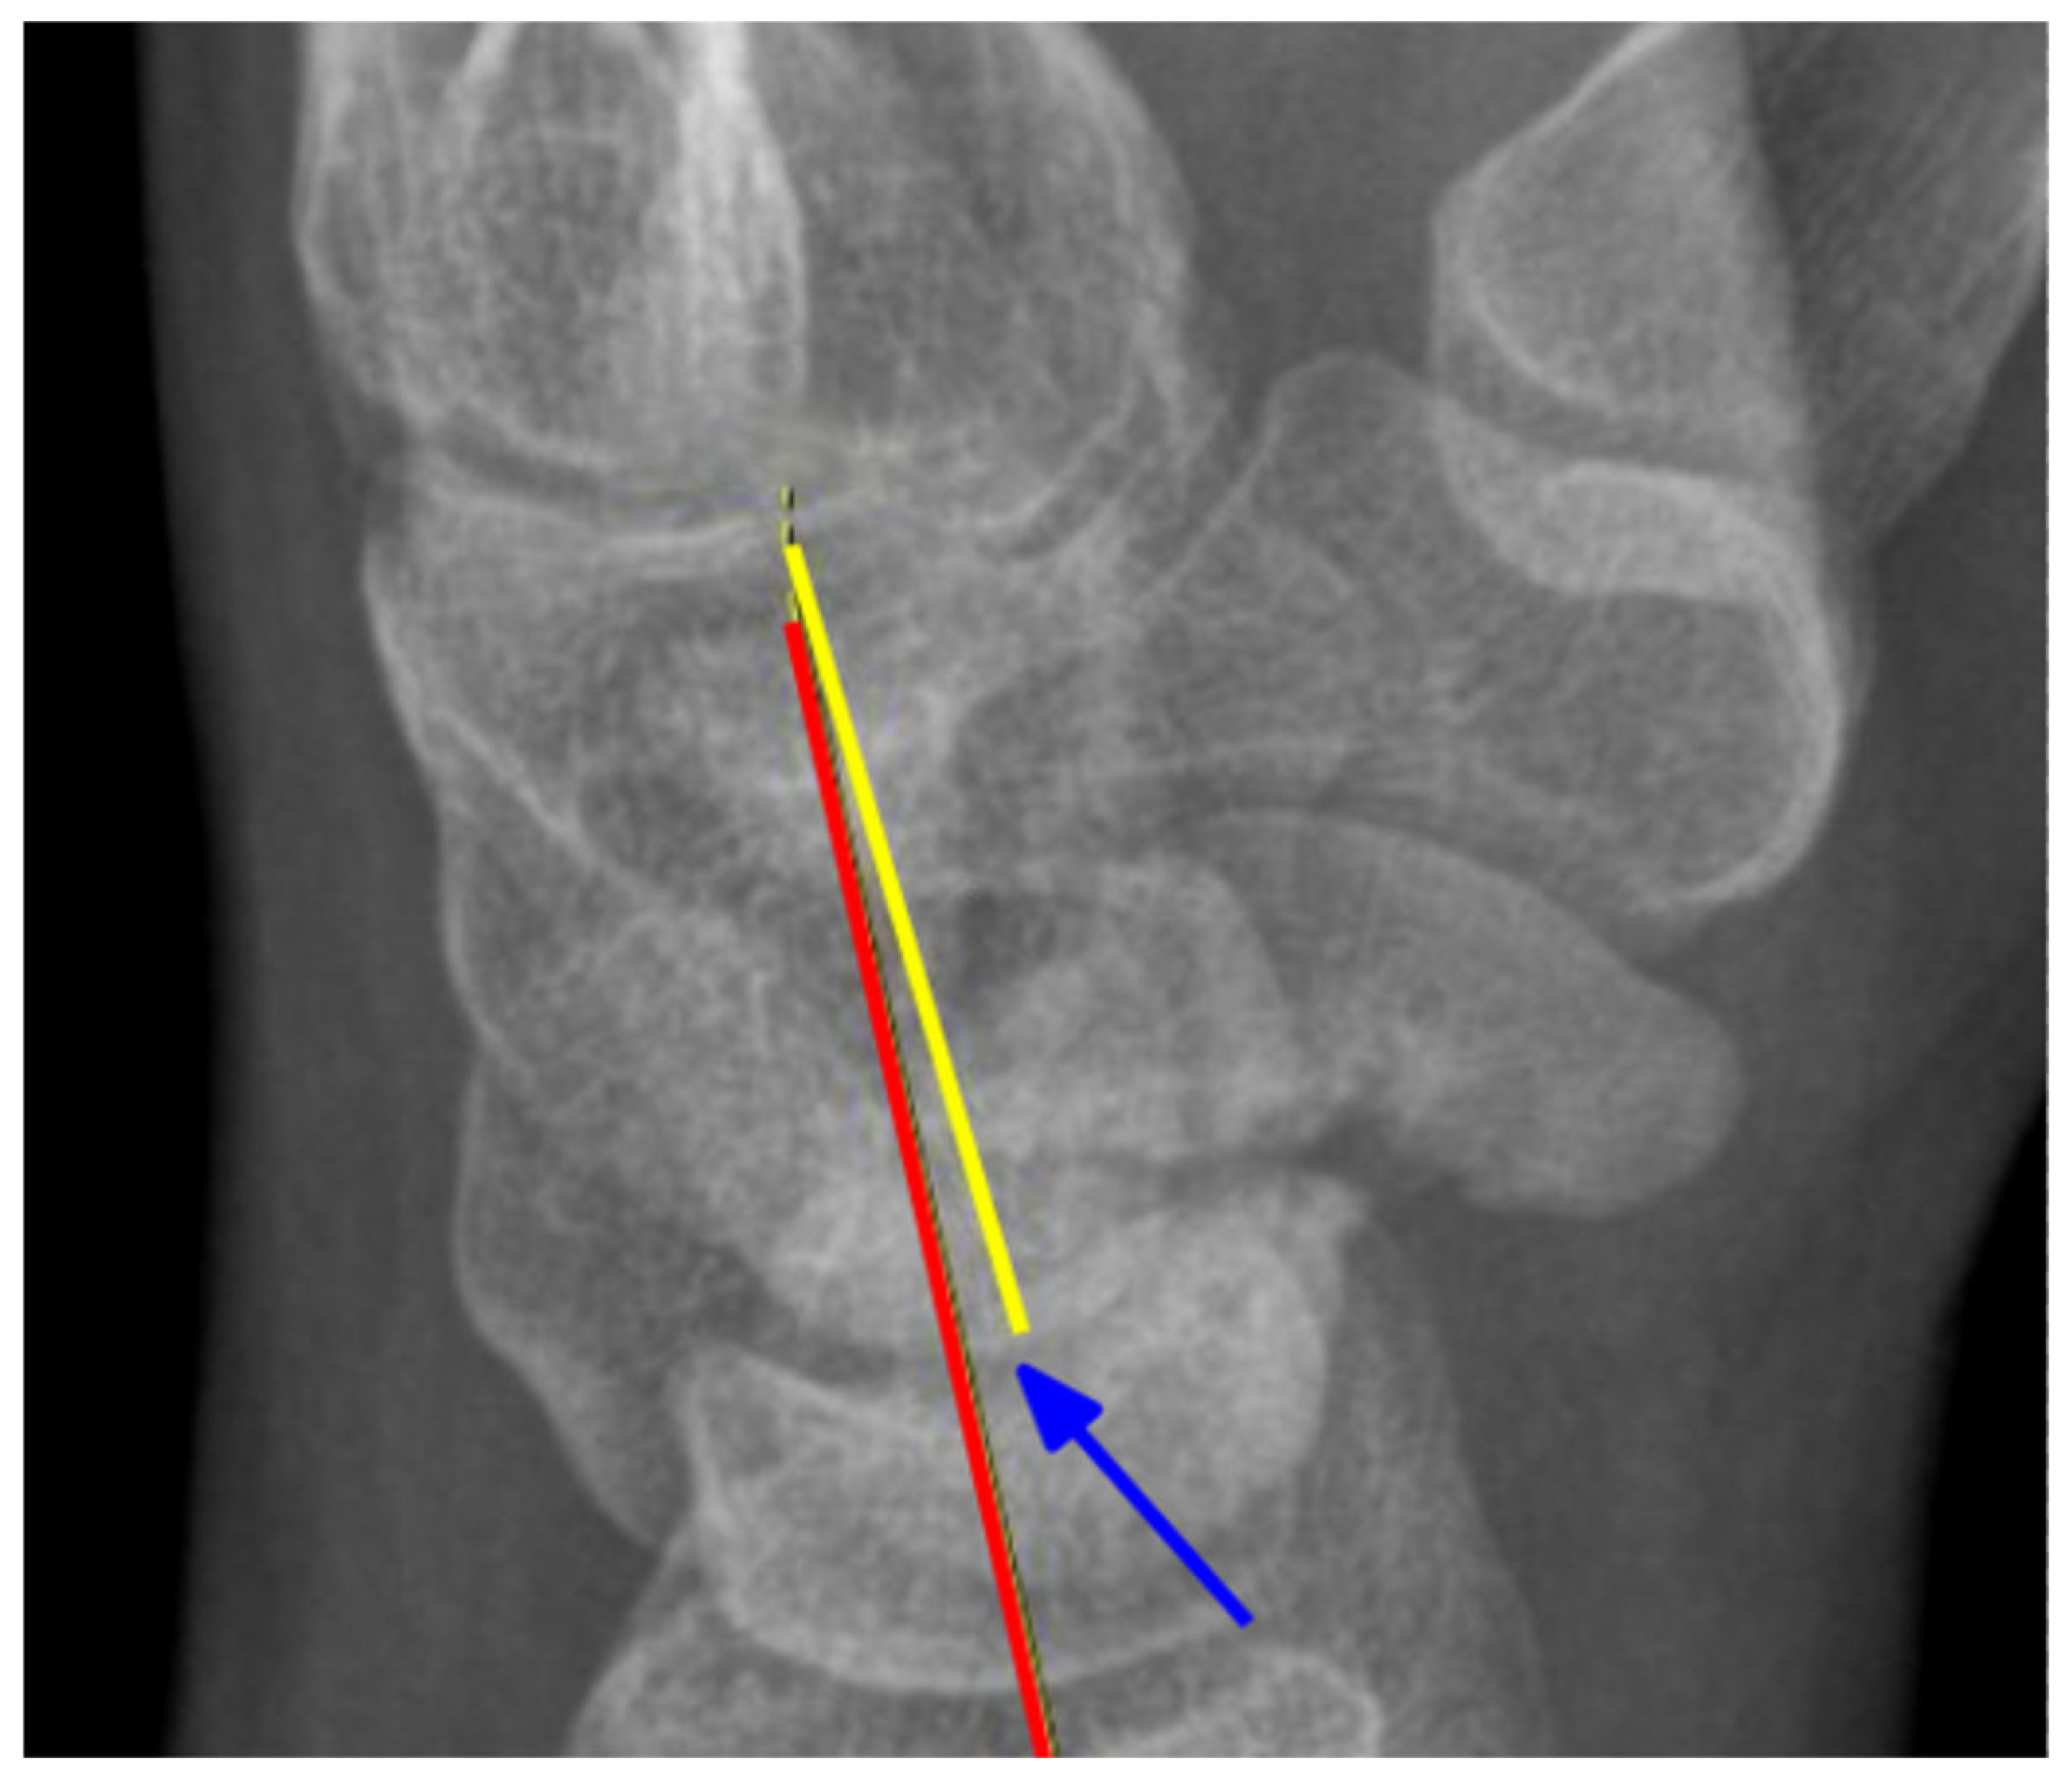

2.2. Radiological Assessment